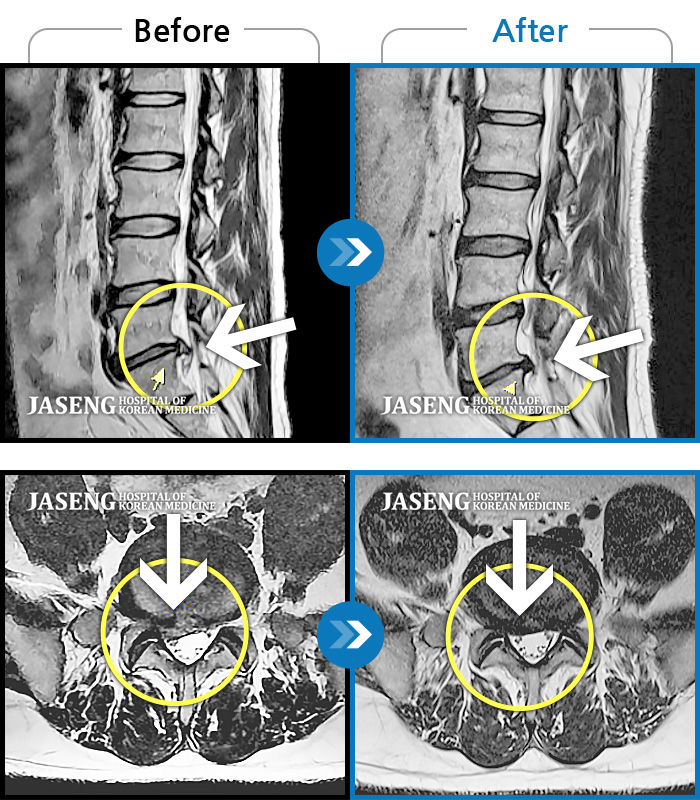

허리디스크

광주 · 김동은 원장

좌측 골반 및 종아리부터 발까지 이어지는 저림과 통증으로 내원하셨습니다.

촬영시기

2023.10.03 ~ 2025.08.14

2025.08.22

조회수 268